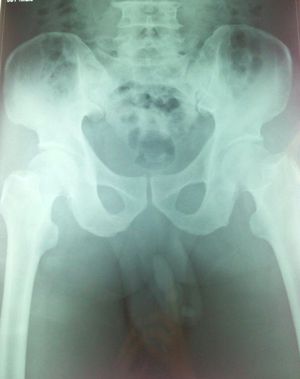

Urethrolithiasis

Urethrolithiasis 4 cm and 1 cm

Xray